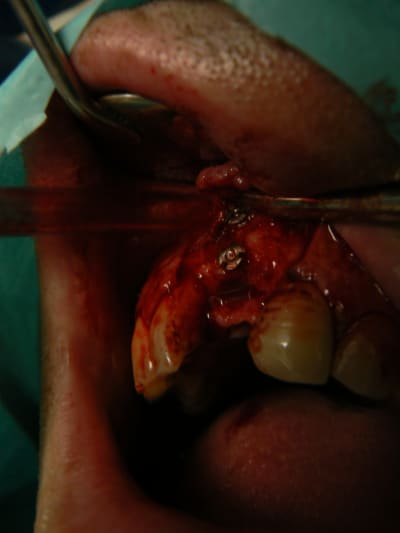

> Ci joint cas avec biobank, très bonne stabilité et consistance a la réouverture

> a 9 mois.

> Pour ce qui est du déficit en GA, j'avais greffé a 5 mois sur la greffe biobank,

> et la vascularisation du greffon osseux n’étant pas abondante, la cicatrisation

> a été difficile.

>

> je dois reintervenir juste en vestibulaire de la 46 qui manque de GA.

j'ai retrouvé, mais c'est le correspondant qui à posé l'implant et les photos sont pas top :(

ceux sont les photos du correspondant .